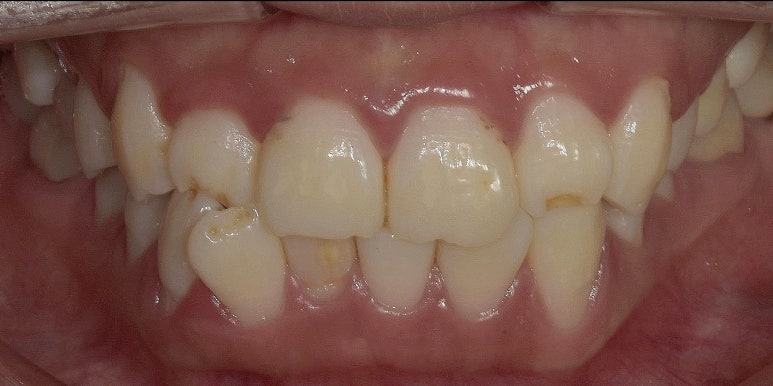

12전치 라미네이트 치료 전 최초 내원 시 모습

2023-06-23

환자분께서는 우선 웃거나 말할 때 보이는 치아 대부분을 라미네이트로 치료하고 싶어하셨습니다.

특히 오른쪽 아랫니(#42)는 치아가 기울면서 앞으로 튀어나와있어

이 치아를 다른 치아와 밸런스를 맞춰 배열을 고르게 만들고 싶어하셨는데요.